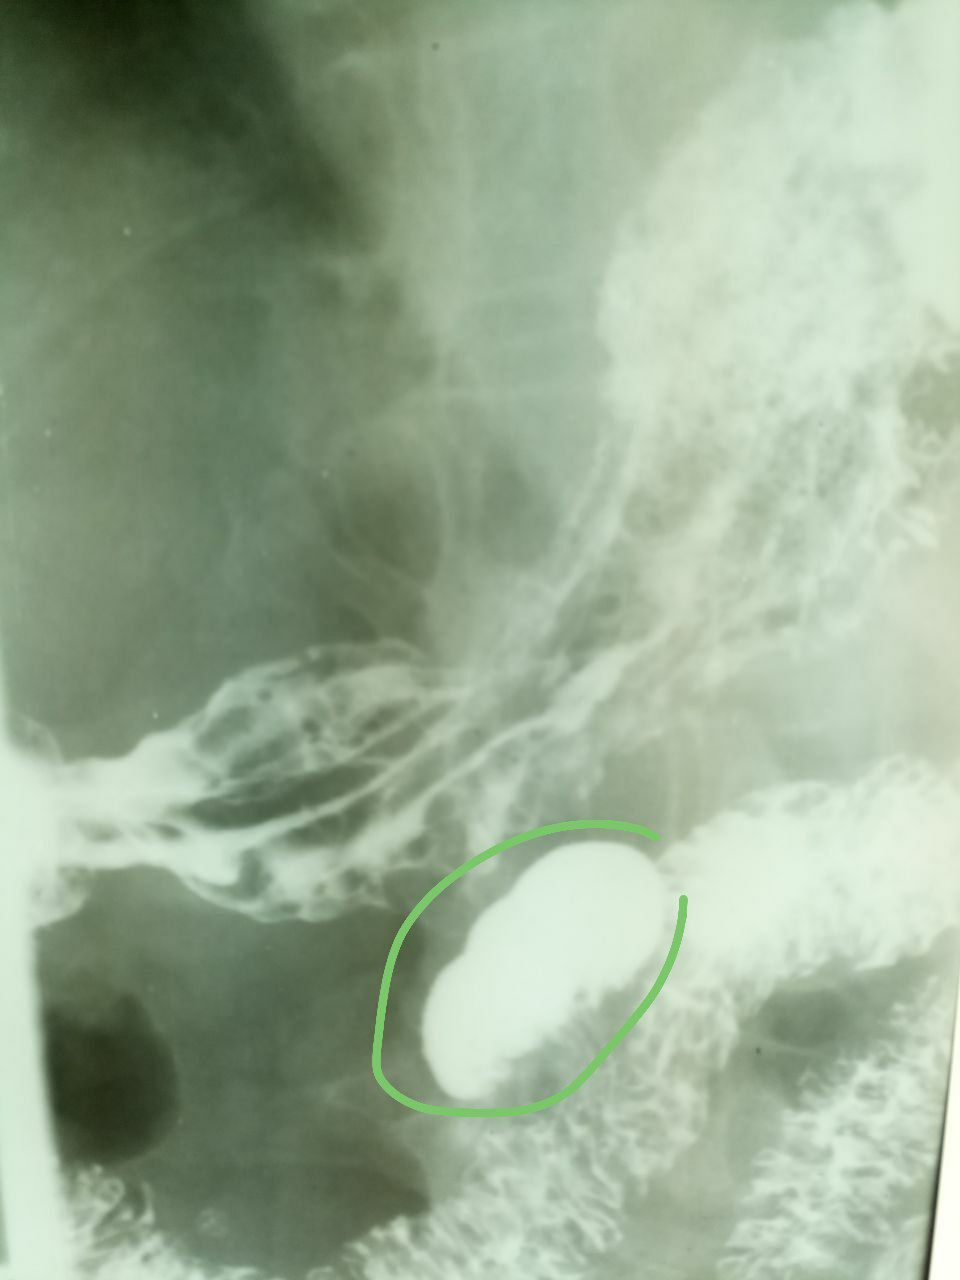

RudSycorsky

Очередной дивертикул 12-перстной кишки.

Именно он. За последние пару лет таких пациентов было человек 7.